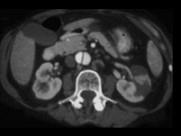

男,54岁,请根据所示图像,选择最可能诊断 ( )A.左侧肾脓肿B.左侧肾囊肿C.左侧肾积水D.左侧肾梗死E.主动脉夹层

问题 男,54岁,请根据所示图像,选择最可能诊断 ( )

选项 A.左侧肾脓肿 B.左侧肾囊肿 C.左侧肾积水 D.左侧肾梗死 E.主动脉夹层

答案 DE